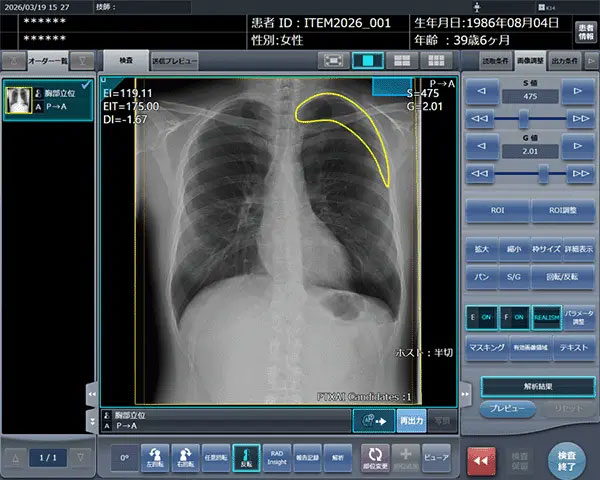

「CXR Finding-i 気胸検出タイプ」により解析された気胸の検出領域を表示

「CXR Finding-i 気胸検出タイプ」は、胸部単純X線画像をAIで解析することで重要所見である気胸の候補を迅速に検出し、候補領域を画像上に表示することで見落とし防止を支援する。病変検出性能を示す指標である感度は95%と高い水準を実現していることに加え、気胸が存在しない画像をAIが正しく陰性(気胸なし)と判断した割合を示す特異度4は96%であり、病変を見逃さないようにしつつ偽陽性も抑制した高精度の検出性能が特長となっている。